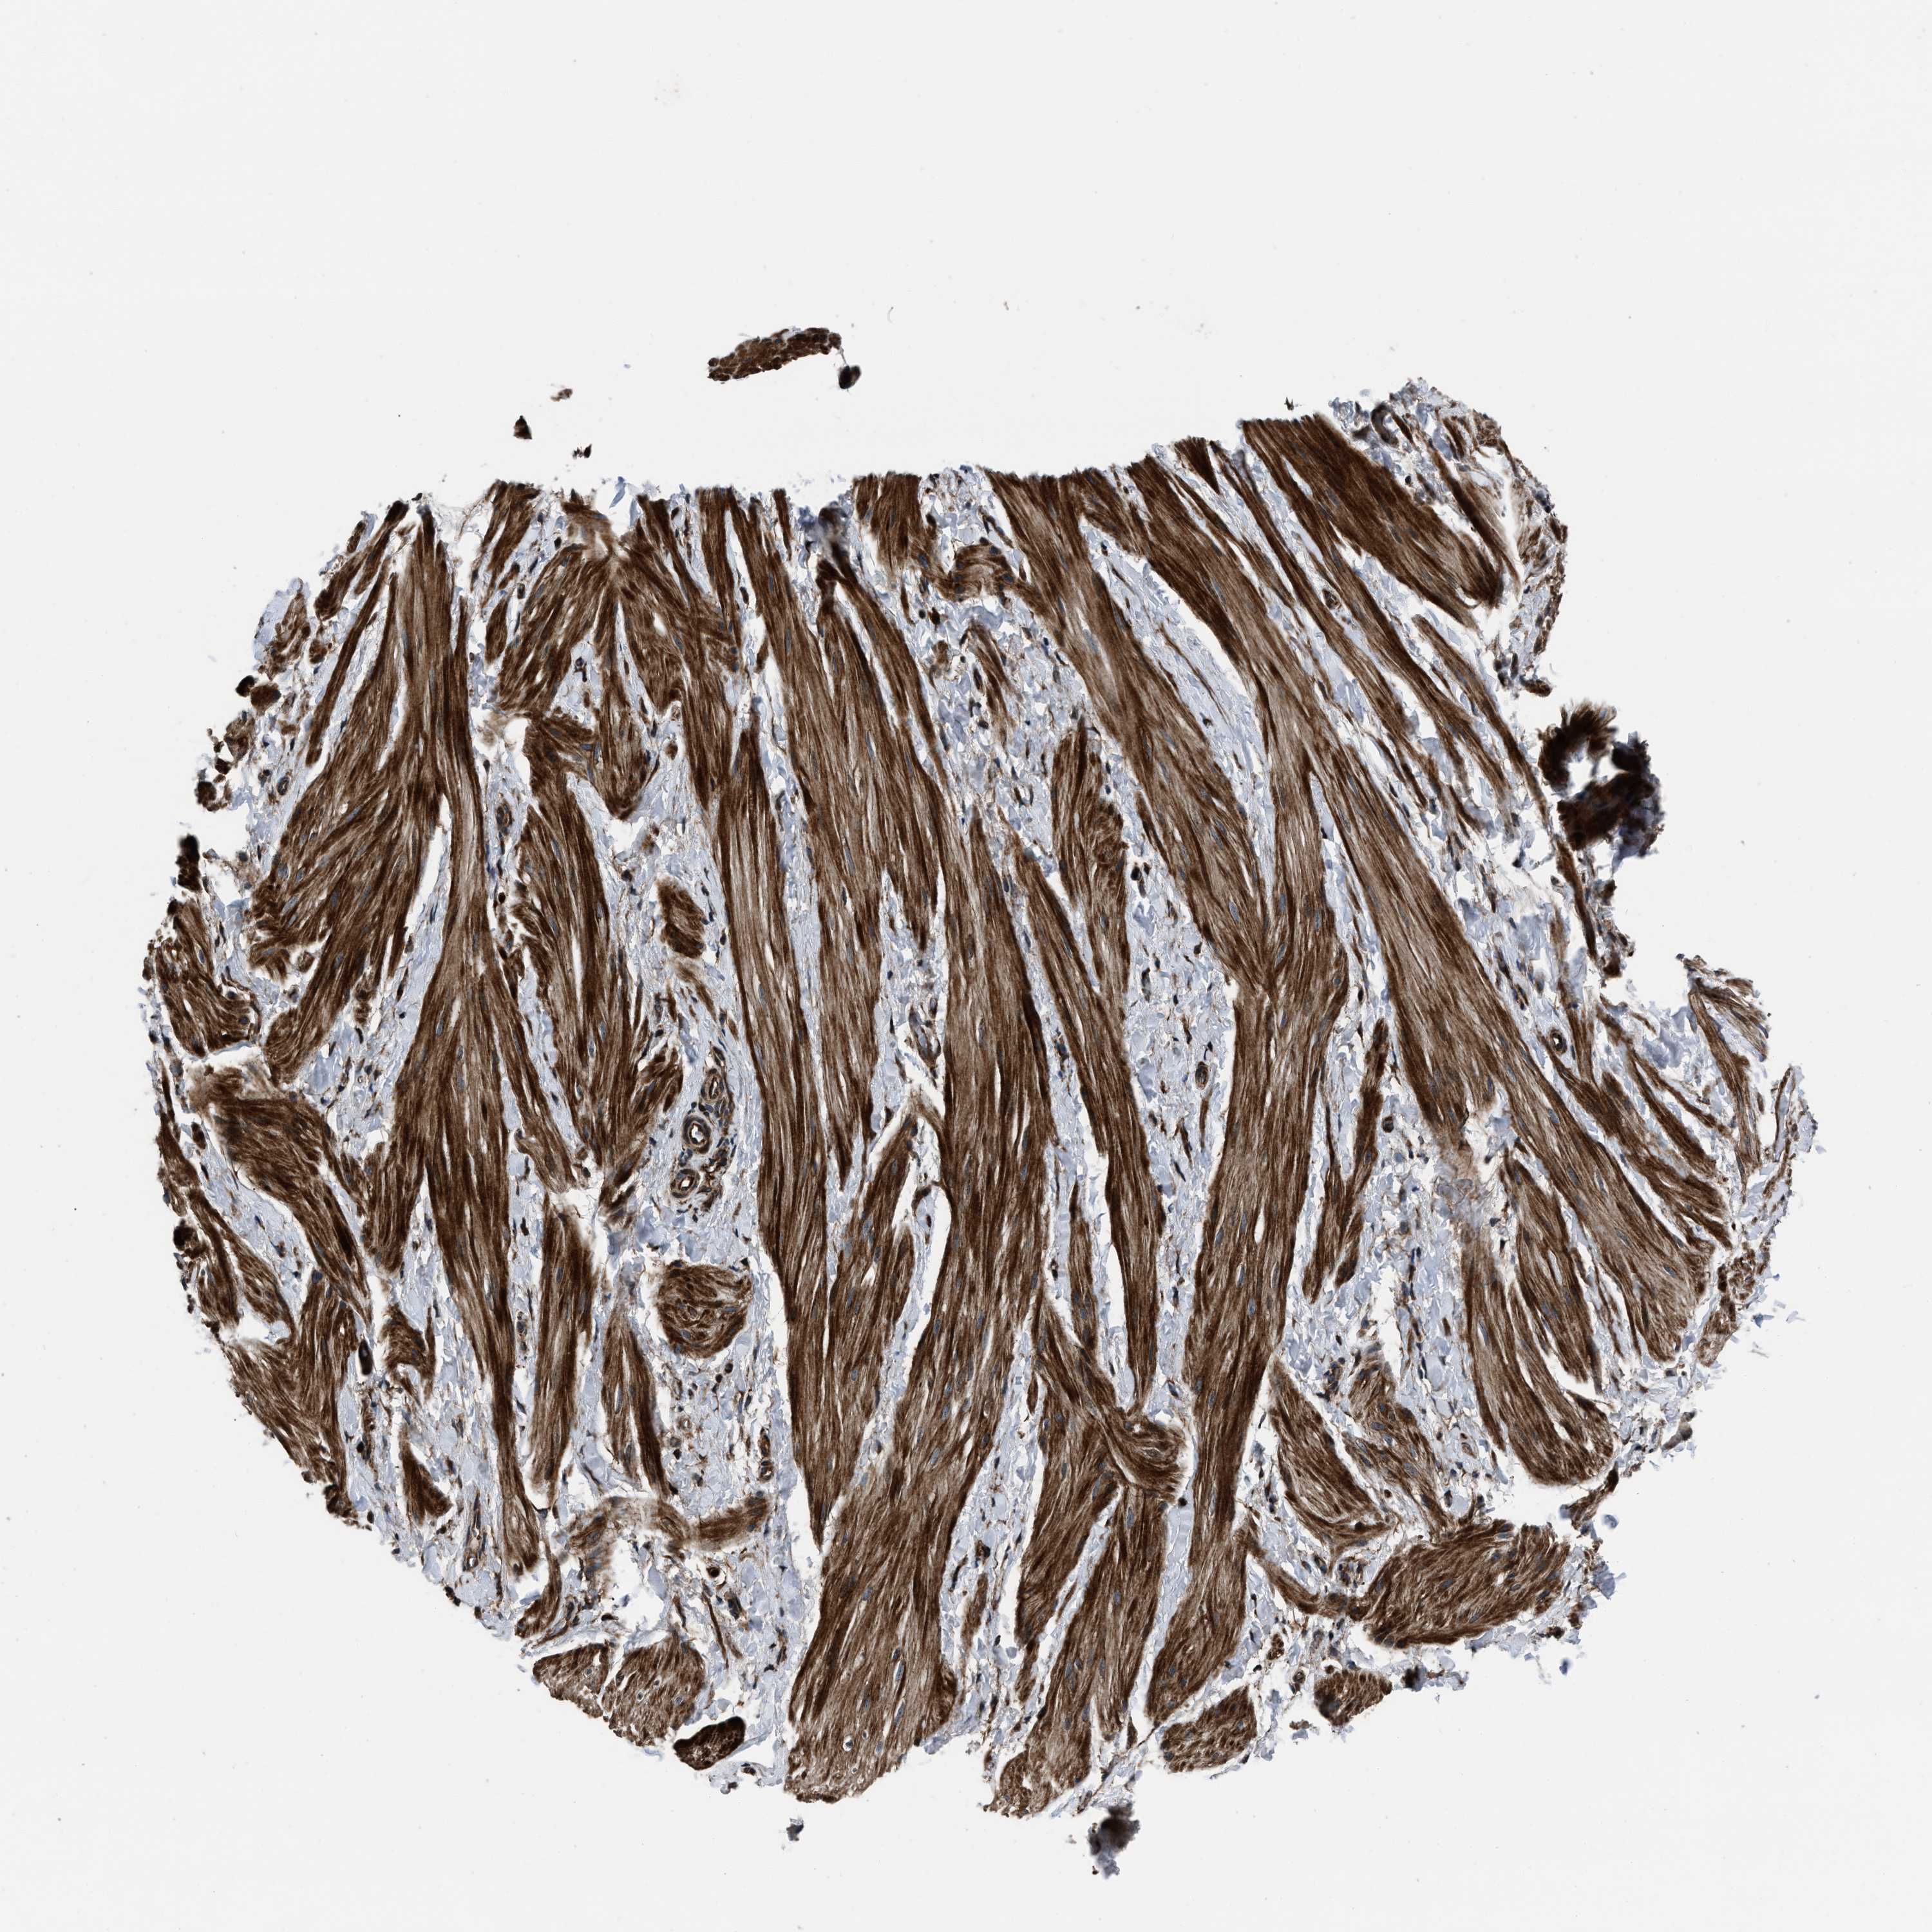

NSD3